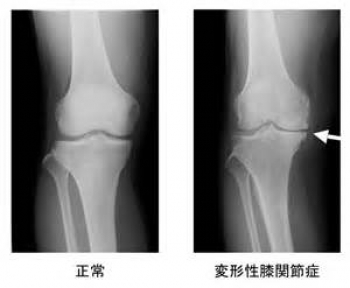

変形性膝関節症

この病気は、高齢者にとても多い病気です。

筋力低下、加齢、肥満などにより、膝軟骨がすり減り、半月板のかみ合わせが緩むことにより、膝の変形を起こす病気です。

もともと、膝の軟骨や半月板は、クッションの役目をしますが、その膝軟骨や半月板が長期間に少しずつすり減り変形することで起こります。

診断

問診、視診、触診、関節液検査、X線検査、血液検査などにより判断します。